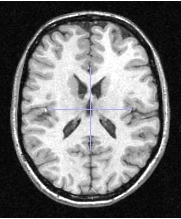

Test image, tex_min = 0, tex_max = 4095

Mode Description Mode_no_binary : fasle Mode_binary : true

less_than to select all the voxels for which value of levels of gray is smaller than the threshold

Threshold1 = 350